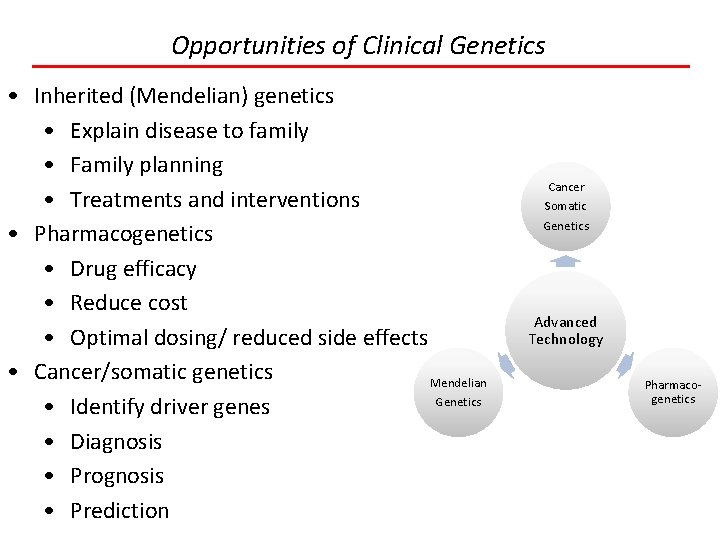

Opportunities of Clinical Genetics • Inherited (Mendelian) genetics • Explain disease to family • Family planning • Treatments and interventions • Pharmacogenetics • Drug efficacy • Reduce cost • Optimal dosing/ reduced side effects • Cancer/somatic genetics Mendelian Genetics • Identify driver genes • Diagnosis • Prognosis • Prediction Cancer Somatic Genetics Advanced Technology Pharmacogenetics